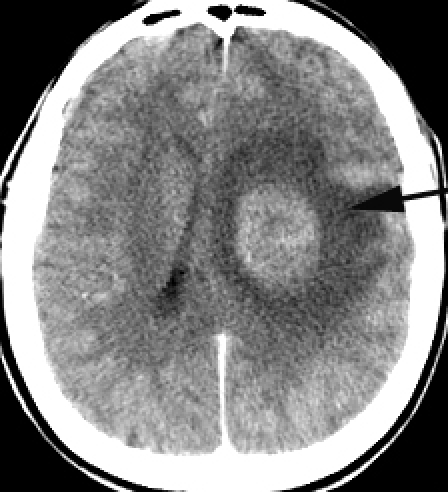

A primarily known brain aetiology causes alteration in intracranial volume then brain edema appears, evolving towards an increase in intracranial pressure. Parenchymatous ICH appears in expansive intracranial processes (tumors, haematomas, cerebral abscesses etc.), in traumatic brain edema, in general intoxication with neural toxins (exogenous or endogenous) etc. [2, 12, 20], (Fig 1).

Fig 1.

A contrast CT image of a deep frontal tumor with brain edema as a case of parenchymatous intracranial hypertension

The direct parenchymatous lesion occurs at first as a result of an intrinsic brain aetiology and of primary alterations in intracranial volume (expansive, compressive, hypoxic or traumatic brain edema). Frequently, the brain edema is sectorial and often there are differences between cerebrospinal compartments. There is a very rapid or a slow increase of ICP above 20 mmHg, but the duration of time of pathologic ICP is short because of decompensation. The parenchymatous ICH can have a complete evolution up to the acute form with brain stem ischemia or brain herniation [2, 11, 12, 25, 28].